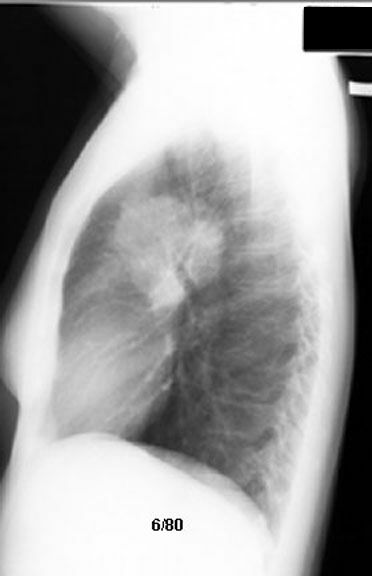

AP Window Nodes - Small Cell Cancer

• Rapid clearance followed by recurrence

• Polycyclic margin